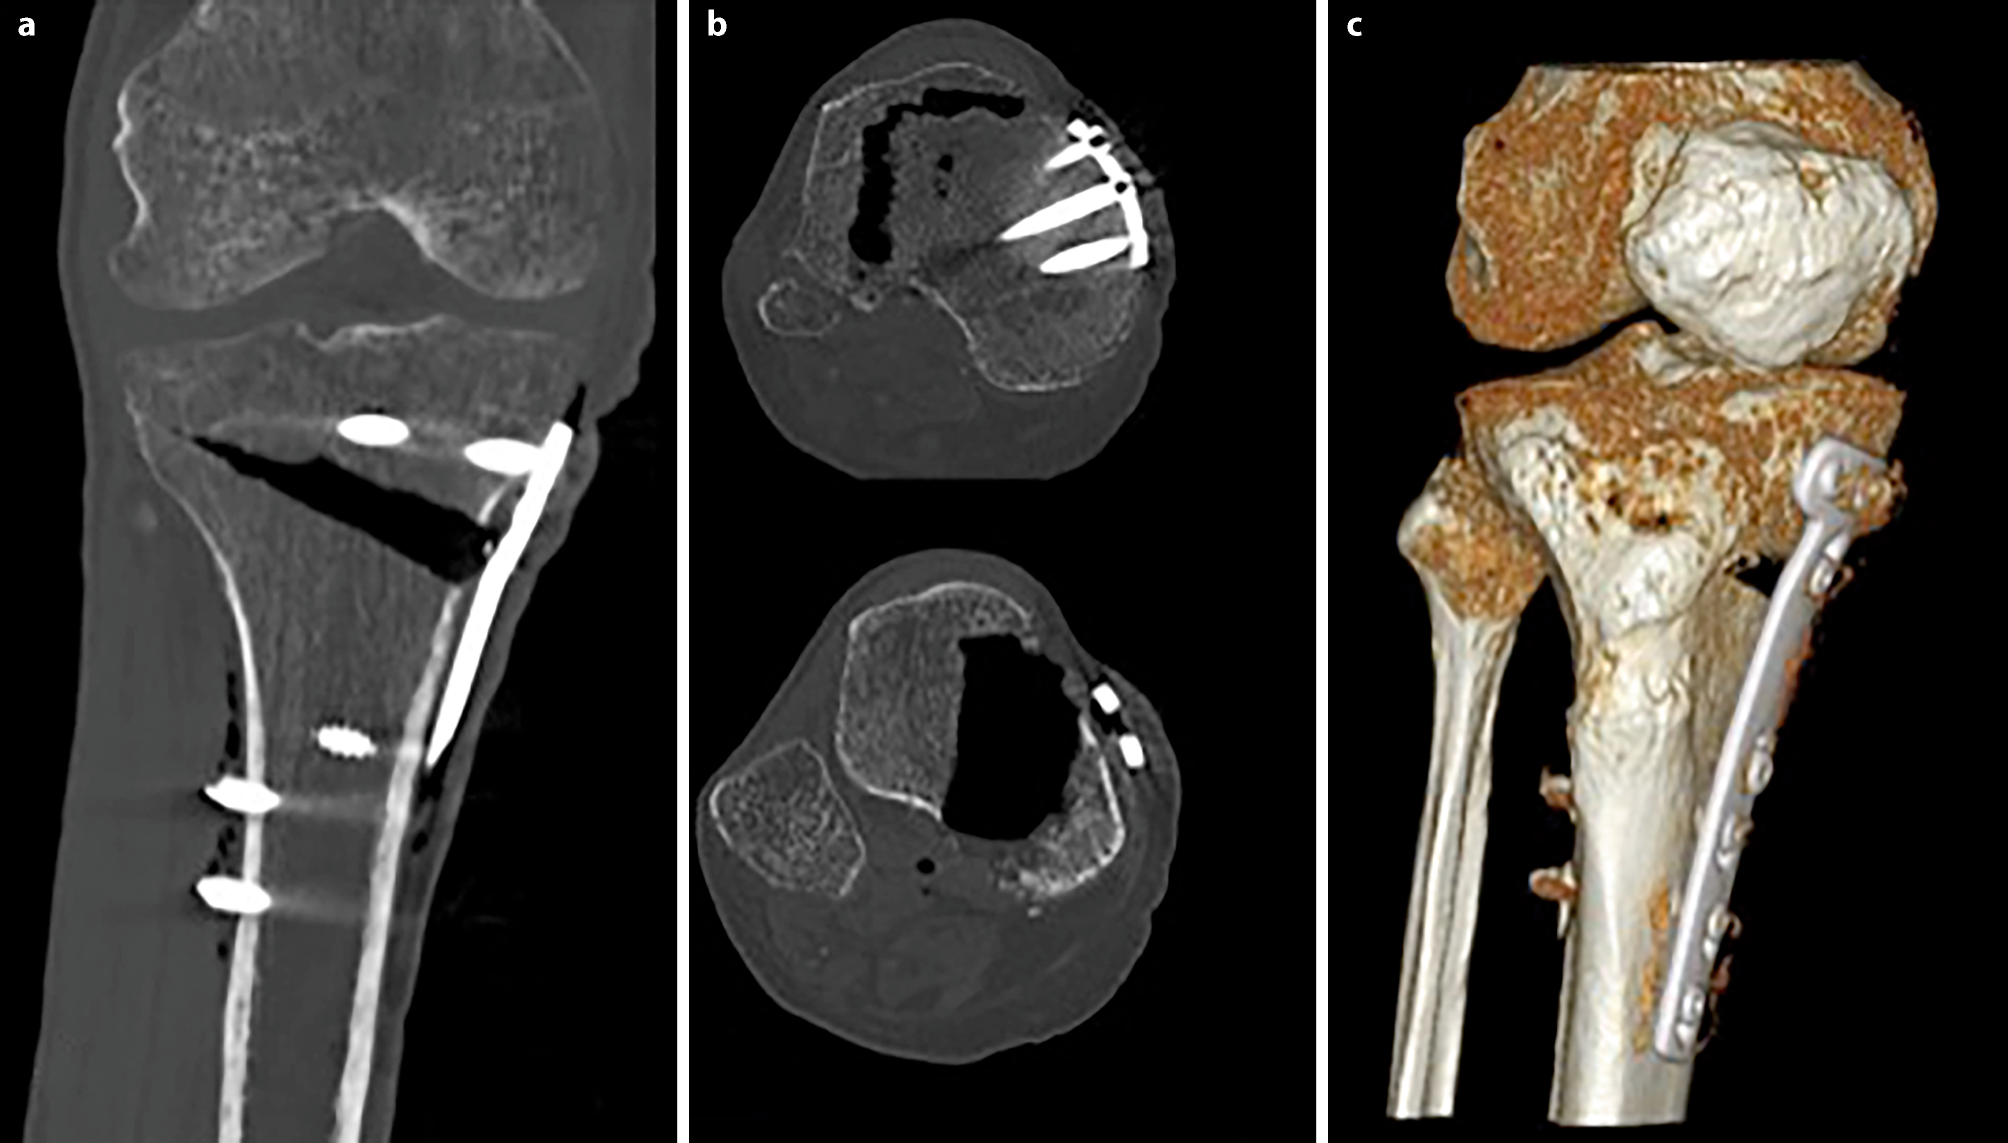

Segmentation of the plate and correspondence between two time points: for registering the two different time points an automatic extraction of the splint is needed (i.e. the Tomofix plate). Due to the high intensities of the splint, a simple thresholding approach was used. The threshold was set at 0.9 using a normalized CT, which is an intensity image containing values in the range 0–1. The range of these values corresponds to the minimum and maximum HU values in the CT image. With this method only the extraction of the Tomofix plate including the screws as a splint mask was achieved. The extracted mask was used for registration. Each splint mask was registered at each follow-up time point to the initial time point using the Elastix toolbox [16]. A three-dimensional (3D) rigid set registration algorithm with six degrees of freedom was used. Additionally, a cubic, multiresolution (four resolutions, with a mean of squared differences similarity) measure was used. This way, the already segmented osteotomy wedge mask at baseline could be transferred according to the position of the plate and to the corresponding follow-up CT image series using the transformation matrix of the registration algorithm. For every follow-up examination obtained 12 weeks postoperatively, the exact location of the wedge from the initial time point was determined and mapped (see Fig. 3).

Fig. 3

The osteotomy wedge is segmented manually at baseline (red) and registered automatically at follow-up (green) examinations using the plate and screws as reference points

Fig. 5

CT scans of cadaveric leg can bypass the obstacle of the overlap of the tibial tuberosity into the osteotomy gap (a shows an AP section image, b shows an axial section image and c shows a 3D reconstruction)

Bild vergrößern